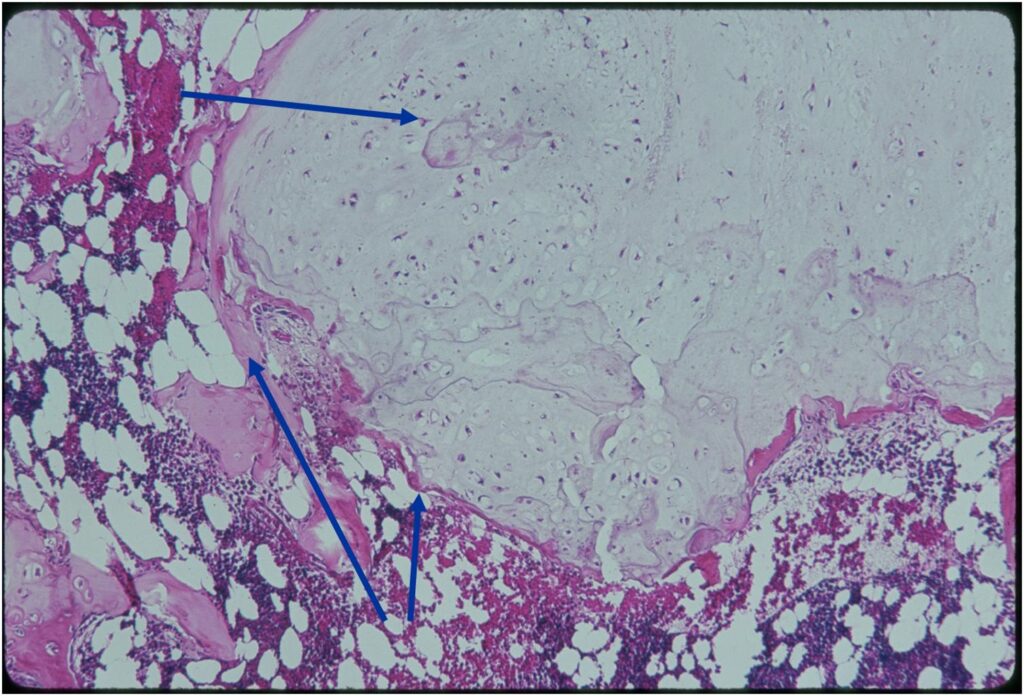

Microscopic Pathology

- Enchondromas are well defined lesions with cartilage arranged in lobules that are separated by fibrovascular septa

- Enchondral ossification may occur around periphery of lobules and when calcified appear as “Rings and Arcs” on X-rays

- Cells are in lacunae and have small dark nuclei

- Low cell count, cells appear bland with few chondrocytes and are similar size and shape

- Although some enchondromas may have areas that are hypercellular and may have two or three cells within a lacunae

- No entrapment or destruction of trabeculae

- There should be no myxoid change in long bone lesions (there is occasional myxoid change in enchondromas of the digits)

- Rests of hyaline cartilage with a lobular growth pattern

- Cells are within lacunae

- Hypocellular with cells spaced apart separated by matrix

- Cells have small nuclei and are similar size and shape (no pleomorphism)

- No mitotic figures

- The matrix has a ground glass basophilic appearance